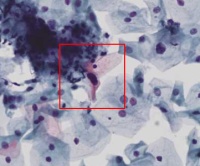

云诊断AC53450

图1

图2

图3

图4

图5

图6

图7